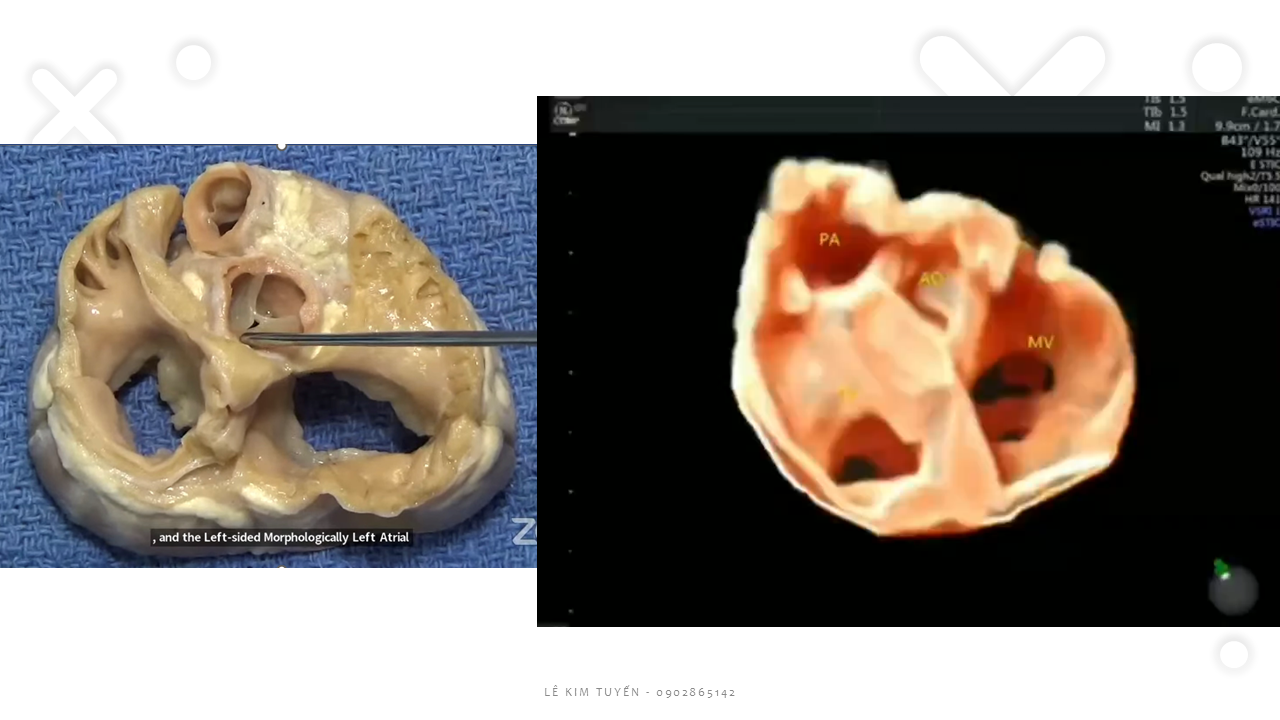

Siêu âm tim thai - Các kỹ thuật hiện đại

TS. BS. Lê Kim Tuyến

Bệnh viện Tim Tâm Đức